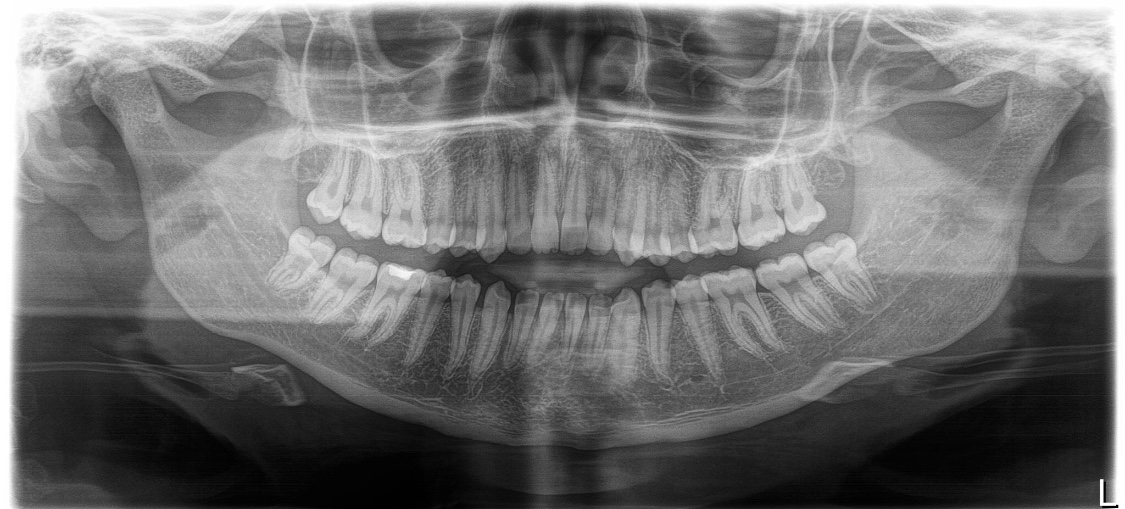

Открытый прикус, помогите разобраться